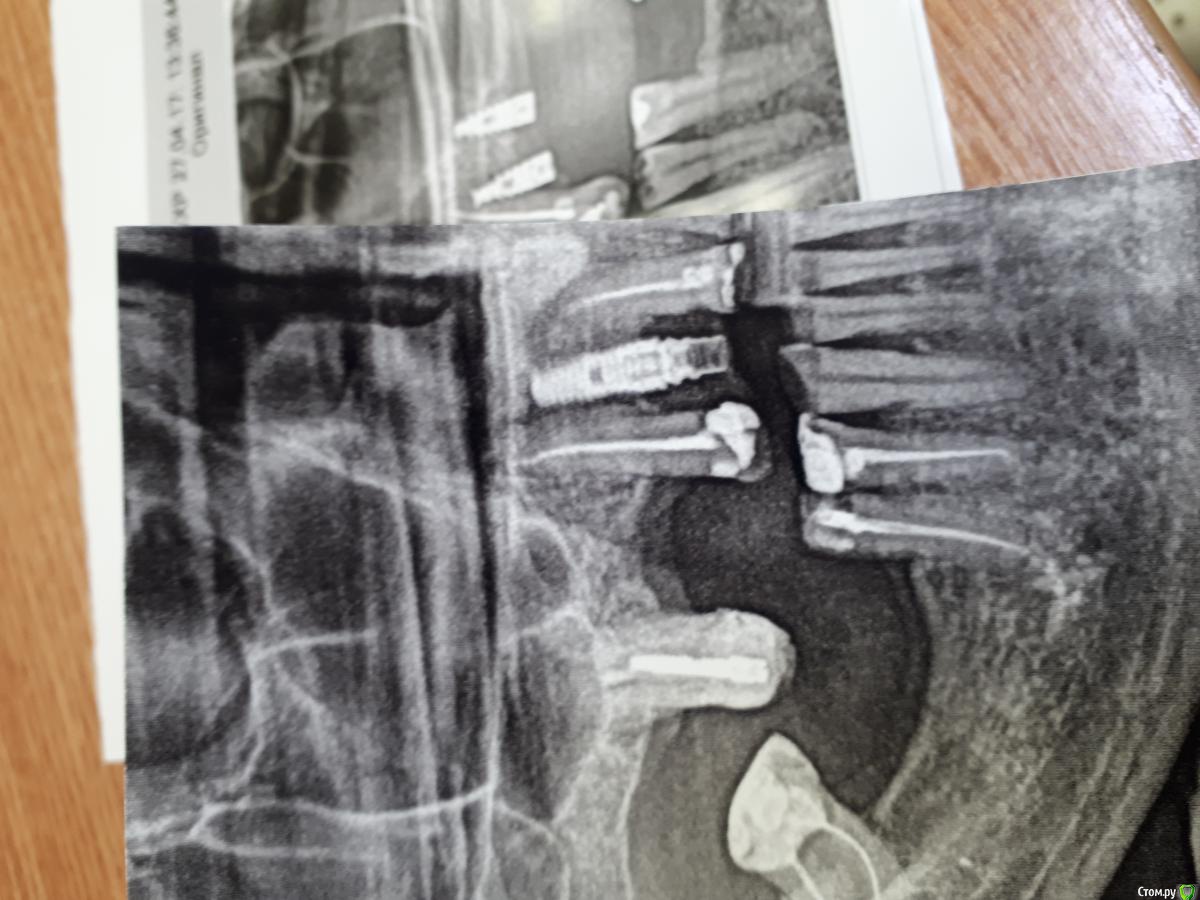

joker_61rus Опубликовано 6 июля, 2018 Поделиться Опубликовано 6 июля, 2018 Доброй ночи. Помогите определить систему,пациент говорит корейские. Отвертка интересная, в виде звездочки. Ссылка на комментарий

АнтонТЛТ Опубликовано 7 июля, 2018 Поделиться Опубликовано 7 июля, 2018 Лучше прицельный показать. В винте не шестигранник, а torx.Dio скорее всего 1 Ссылка на комментарий

dok1 Опубликовано 8 июля, 2018 Поделиться Опубликовано 8 июля, 2018 У дио точно торкс. По рентгену похоже новая линейка дио. 1 Ссылка на комментарий

dok1 Опубликовано 9 июля, 2018 Поделиться Опубликовано 9 июля, 2018 Вроде на снимке имплант с агрессивной резьбой? А старые дио более нежные.... но могу и неразглядеть чтото. Ссылка на комментарий